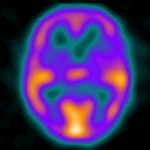

利用放射性核種或者是其他方法所測量出來的正常左心室搏出率平均約為65%,範圍在55-75%之間,在核醫的測量方式中,是以左心室ROI的count數來做計算,我們在心電圖的輔助下,可以將一次心跳的影像,切割成16或是32張影像來儲放,然後分別根據這些影像中左心室ROI的count數,就可以畫出一個能呈現左心室收縮和舒張時count數變化的曲線圖,然後以其中count數最低的就是end-systolic(ES)心室收縮的末期,count數最高的就是end-diastolic(ED)心室舒張的末期,心室的搏出率就可以表示成:

EF=(ED-ES)/ED。

那麼如果要計算右心室的搏出分率,可不可以用同一份資料來處理呢?因為在LAO的角度下,左右心室可以分割的很清楚,因此看起來似乎可行性也蠻高的,其實不然,因為就正常的心臟結構來說,右心室是位於身體的較深處,不像左心室是位於體內的淺處,雖然LAO的角度能夠將左右心室區隔開來,可是在這個角度,右心室和右心房會有部分的重疊,因此在計算右心室的搏出分率時,會有低估的情形,因此要正確的計算右心室搏出分率,只有利用first-pass這個方式才行,照相的角度為RAO,在這個角度可以得到較佳的右心室影像,也因為是first-pass的關係,我們不用去擔心右心房或者是左心室在這個角度時可能會發生的重疊影像,我們只需要設定好我們所需要的影像片段,就是放射性核種自右心房流進右心室,然後再流到肺部的這個時間內的影像即可,雖然說在處理first-pass的資料時需要注意相當多的細節,不過只要影像處理得當,所得出來的數據和ECG-gated MRI的吻合度相當的高,以正常的個體來說,平均值為59%,範圍則是在45-70%之間,因此這題的答案是(C)55-75%。我將這個檢查所處理出來的結果放在下面,讓大家參考一下。

這是在LAO角度下所見到的心臟舒張和收縮末期的影像。 |

這是左心室的ROI |

左心室count數變化曲線圖 |

這是右心室的ROI,可以看到和右心房有部分的重疊 |

右心室count數變化曲線圖 |